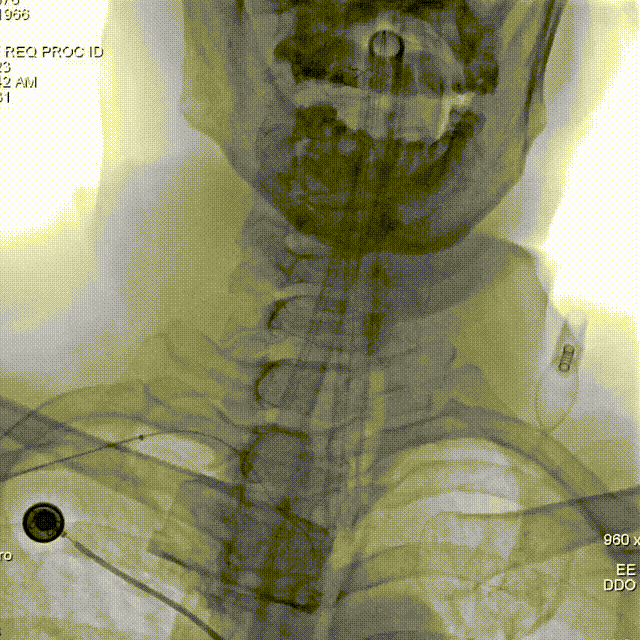

桡动脉入路:

Lattice支架输送:

微导管到位。